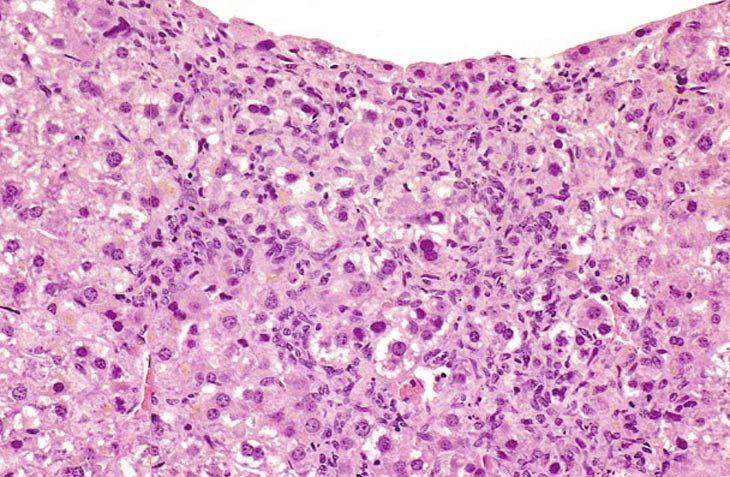

This change was originally diagnosed as endothelial cell proliferation. Based on the H&E stained sections, it is not possible to definitively identify the proliferating sinusoidal lining cells as endothelial cells but some have cytomorphological features consistent with endothelial cells. Low and high magnifications of endothelial cell hyperplasia.